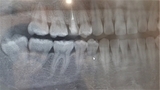

レントゲン検査の役割: レントゲン撮影は虫歯の進行具合を評価するために重要な手法です。レントゲン画像を通じて、歯の内部の虫歯の進行状況や根の状態を見ることができます。